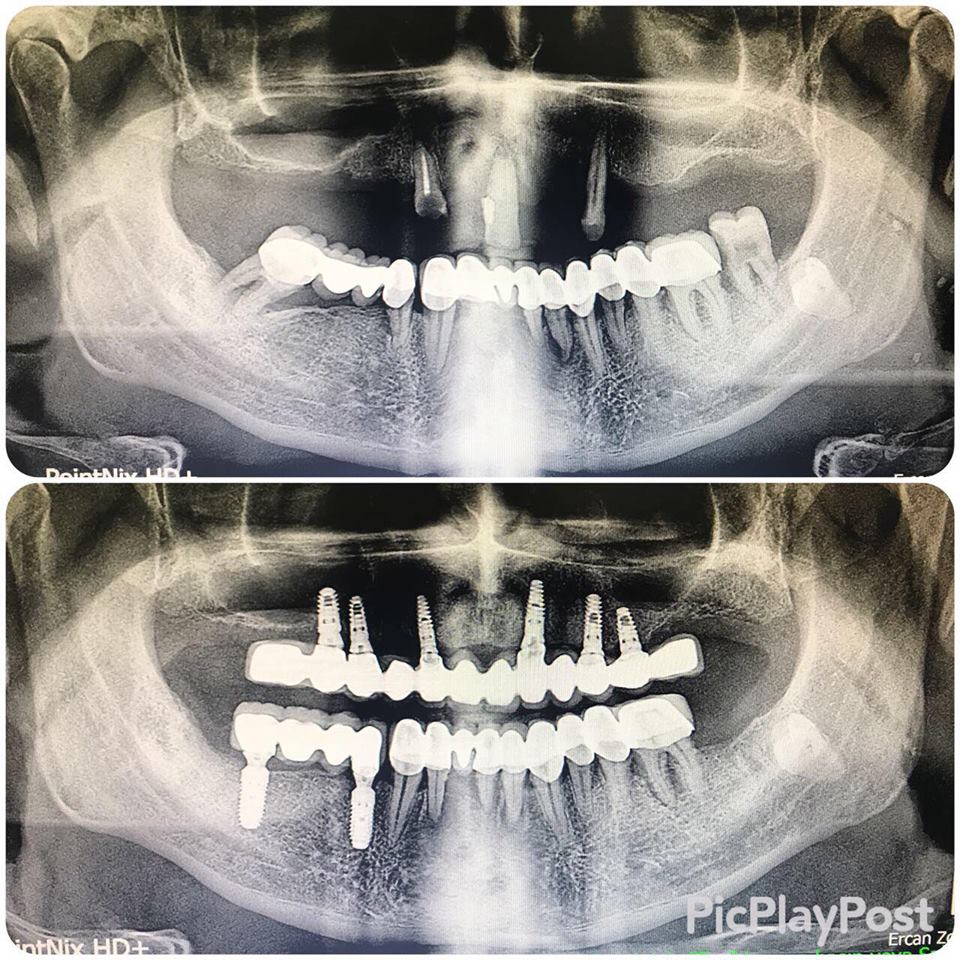

İMPLANT TEDAVİSİ

implant tedavisi